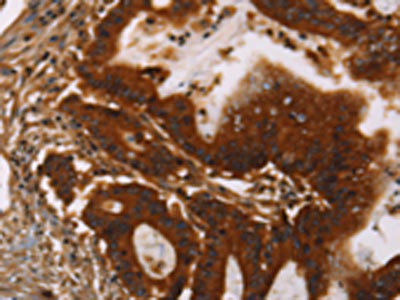

The image on the left is immunohistochemistry of paraffin-embedded Human colon cancer tissue using CSB-PA029827(GPA33 Antibody) at dilution 1/30, on the right is treated with fusion protein. (Original magnification: ×200)

The image on the left is immunohistochemistry of paraffin-embedded Human gastric cancer tissue using CSB-PA029827(GPA33 Antibody) at dilution 1/30, on the right is treated with fusion protein. (Original magnification: ×200)